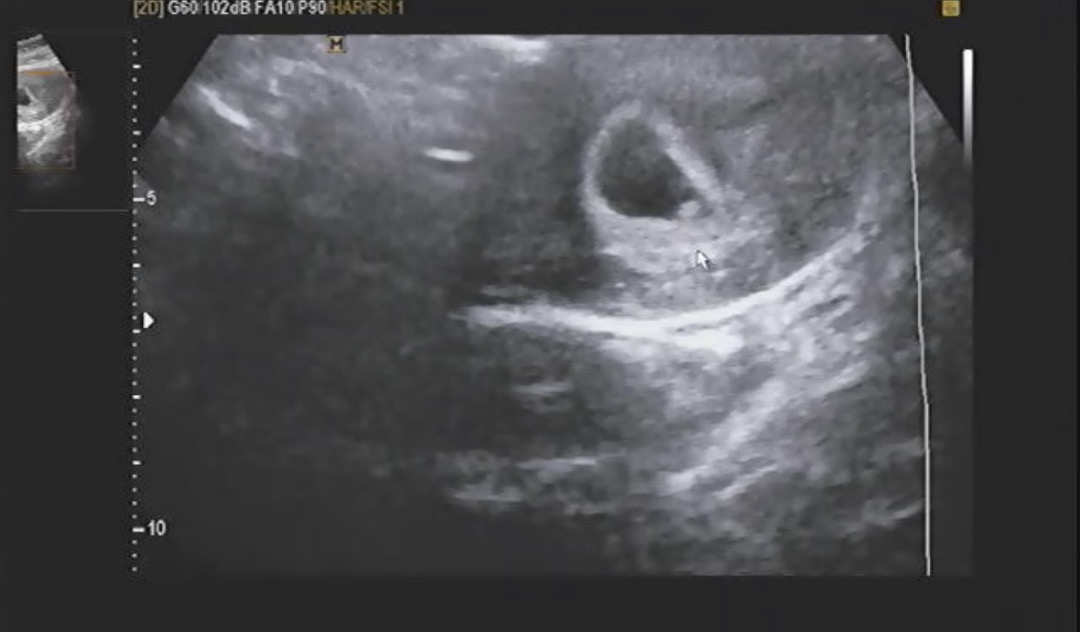

6주0일차 초음파 봐주세요ㅠㅠ

6주0일 초음파를 보러갔는데 저렇게 흐릿하더라구요 심장소리도 들려주시는데.. 전 들리지도 않는데 선생님은 110bpm이라 괜찮다 하시고.. 다른 촘파 사진들 보면 난황에 애기가 다이아몬드 모양처럼 보이던데 전 흐릿해서 잘 보이지가 않아서요ㅠ 괜찮은거 맞을까요?? 첫 임신인데 걱정만 되네요

초음파 각도에 따라 잘 보이기도 안보이기도 하더라구요! 이상 없다고 하시면 아무 문제없을게용

다음 진료 때 가면 흔히 알고 계시는 다이아모양 난황 확인할 수 있으실거에요~ 저도 저렇게 작게 보여서 왜 난 다를까 했는데 그 다음주에 가니 다이아반지처럼 잘 보였습니다 ㅎㅎ 맘편히 걱정 안하셔도 됩니다🙂

심장소리 들으셨으면 어느정도 안심해도 되실거예요 bpm도 주수에 맞구요 초음파 화질이 좀 안좋아보이긴하지만 의사도 별말 안한거면 괜찮을겁니닷!!